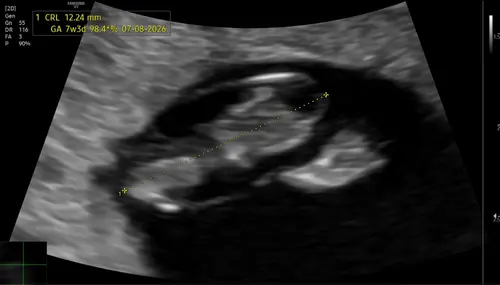

Afgelopen maandag ongeveer 8 weken ❤️ van kruin tot stuit 1,6cm